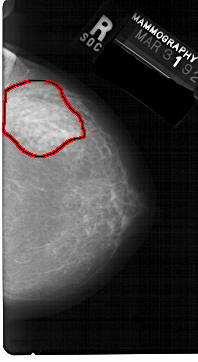

A_1599_1.LEFT_CC

LEFT_CC LINES 5491 PIXELS_PER_LINE 3316 BITS_PER_PIXEL 12 RESOLUTION 43.5 OVERLAY

FILE: A_1599_1.LEFT_CC.OVERLAY

TOTAL_ABNORMALITIES 1

ABNORMALITY 1

LESION_TYPE CALCIFICATION TYPE PLEOMORPHIC DISTRIBUTION CLUSTERED

ASSESSMENT 4

SUBTLETY 1

PATHOLOGY MALIGNANT

TOTAL_OUTLINES 1

BOUNDARY